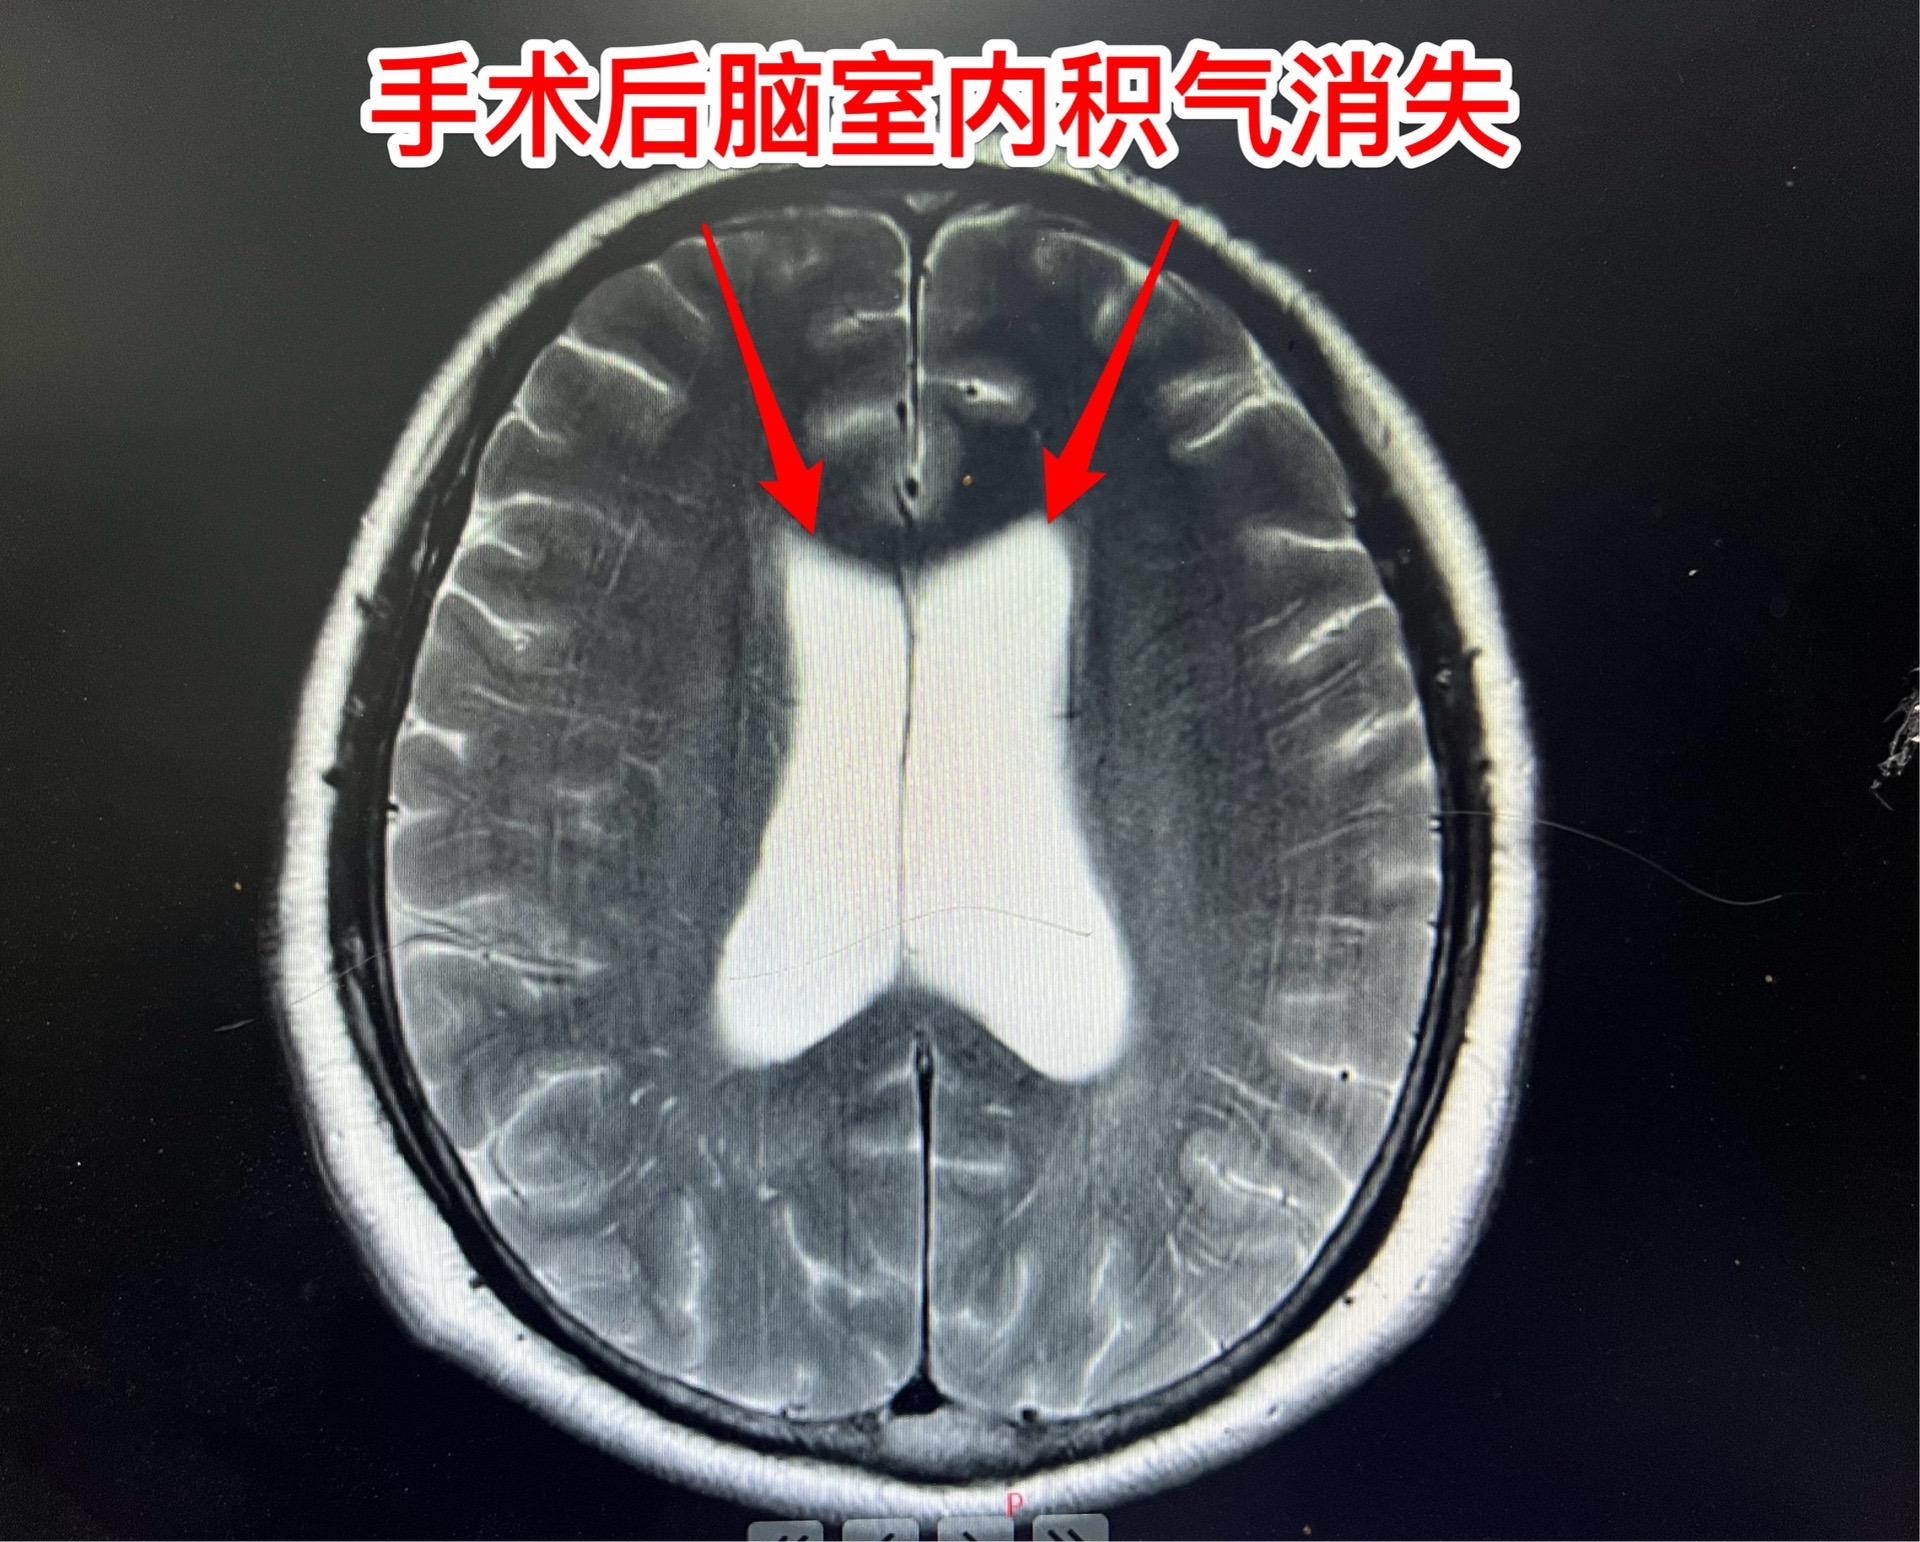

吃药能让垂体瘤消失?这不是传说。垂体瘤中有一种特殊的瘤叫泌乳素瘤,可以通过吃药就化掉了!这不是传说!最常用的药叫溴隐亭! 但是,切记:如果停药了,肿瘤又会长出来的! 这个51岁的承德市男性,3年前因视力下降到医院检查发现了垂体瘤,经过化验泌乳素,被确诊为泌乳素瘤。口服溴隐亭这个神药,肿瘤变小了,吃药两年后病人因为头晕、行走困难而停药。停药一年后肿瘤又复发了,肿瘤体积很大,侵蚀了垂体窝骨质进入蝶窦内! 2024年10月25日在我科复查泌乳素,显示泌乳素水平远远